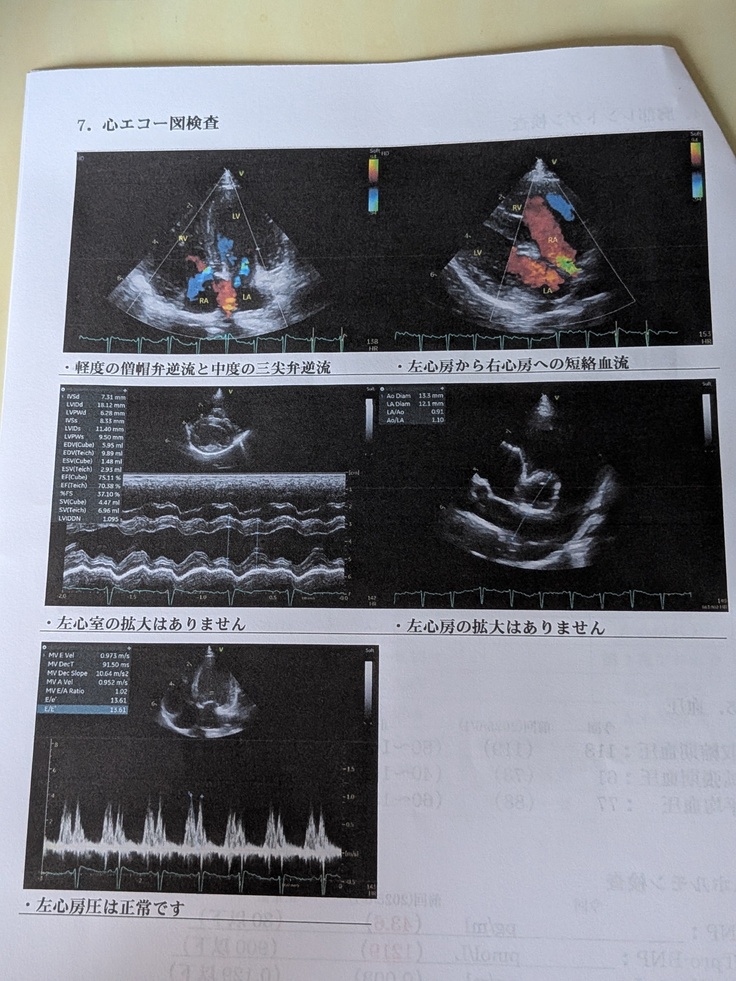

先週末の7月13日(日)、術後半年間毎月通うことになっておりました、最後の定期検診を受けてきました‼️‼️

今回もとっても順調✨✨若干、前回より右心室の拡大は見られるものの、問題ない範囲とのこと😌

その他、継続的に三尖弁の逆流は見られるものの、問題なし‼️

※病院の報告写真と“すあま”の写真を掲載します✨